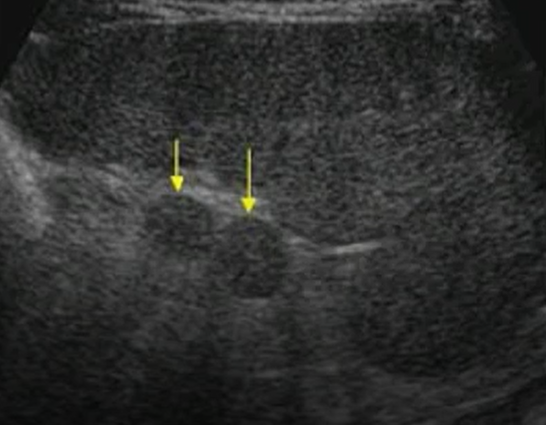

What is the most common congenital variant of the spleen?

Accessory spleen

Describe an accessory spleen.

Small round/ovoid structure of same echogenicity/texture as spleen tissue

Where is an accessory spleen most often found?

Splenic hilum

What is an accessory spleen often confused with?

Lymphadenopathy

How is accessory spleen verified?

By demonstrating vascular connection to the spleen